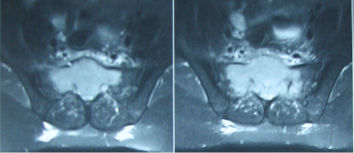

KORDOMA

Sakrum ve alt omurga seviyelerinde kalan embriyonik doku artıklarından kaynaklandığına inanılan, düşük dereceli, yavaş büyüyen, lokal destrüksiyon yapan habis bir kemik tümörüdür. Genellikle 40-70 yaşları arasında ve erkeklerde biraz daha fazla görülür. Sakral kordomalar, önlerindeki boşluğa doğru yavaş yavaş ve ağrısız olarak büyüdükleri için ancak geç dönemde şikayetlere neden olurlar. Hastalar uzun süre oturmakla alt omurga bölgelerinde ağrı, zaman zaman kabızlık ve güç tuvalete çıkma şikayetleri ile hekime başvururlar. Hastalığın ileri dönemlerinde bacaklarda his kaybı, mesane, barsak ve cinsel fonksiyon kaybı gibi nörolojik bulgular ortaya çıkar. Bu dönemde rektal muayenede sakrumdaki kitle ele gelebilir.

Grafide sakrumda orta hat yerleşimli, belirsiz sınırlı, litik bir kitle görülür. Düz grafide görüntü almak çok zordur. MRI incelemesi, tümörün tüm uzanımını, öndeki rektum, mesane, damarlar ve özellikle sinir kökleri ile ilişkisini gösterir. BT’de kemikteki destrüksiyon en iyi şekilde görülür. Ayırıcı tanıda dev hücreli tümör, anevrizmal kemik kisti, kondrosarkom dikkate alınmalıdır.

Kordomada kemoterapi ve radyoterapinin etkisi yoktur, buna karşın lokal tekrarlama eğilimi çok yüksektir. Yetersiz cerrahi yapıldığında lokal nüks gelişir. Esas tedavisi cerrahidir. İmkan dahilinde geniş rezeksiyonla çıkartılmalıdır. Teknik olarak tam çıkartılamaz ise radyoterapi (RT) uygulanmalıdır. Geniş rezeksiyon yapıldığında 5 yıl yaşam şansı %73, 10 yıl yaşam beklentisi %58’dir. Hastaların %30’unda metastaz görülür.